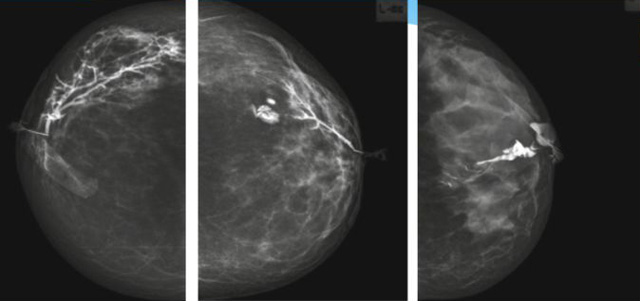

乳腺導管內(nèi)乳頭狀瘤分為以下兩個,位于乳暈區(qū)大導管的中央型乳頭狀瘤,起源于末梢導管小葉單位的外周型乳頭狀瘤。外周型乳頭狀瘤常常沒有明顯的的臨床表現(xiàn),常因X線或乳腺超聲設(shè)備檢查發(fā)現(xiàn)。重點要關(guān)注的是中央型乳頭狀瘤,發(fā)生于任何年齡的女性,以40~50歲者居多。它表現(xiàn)為:單側(cè)乳頭溢液,特別是血性溢液少數(shù)病人可在乳暈區(qū)觸及腫塊。從病理學上面講表現(xiàn)為導管上皮和間質(zhì)增生形成有纖維脈管束的乳頭狀結(jié)構(gòu)。這是它一個病理學上的表現(xiàn)。它的超聲表現(xiàn)為:病變導管囊狀擴張呈無回聲,內(nèi)可見乳頭狀低回聲或中等回聲。乳暈處的導管擴張,管腔內(nèi)可見邊界清楚的,低回聲實性結(jié)節(jié)。外周型導管內(nèi)乳頭狀瘤可,表現(xiàn)擴張為為低回聲的實性結(jié)節(jié),CDFI:部分腫瘤可顯示為軸心性的看到血流信號。乳腺增生癥:可見導管擴張,內(nèi)無乳頭狀實性回聲,導管內(nèi)乳頭狀癌:囊內(nèi)乳頭狀癌病變較大,不規(guī)則,厚基底,血流豐富。以囊性為主的混合回聲,形態(tài)不規(guī)則,內(nèi)見實性低回聲實性低回聲可見少量血流,病理為囊內(nèi)乳頭狀癌。

乳腺超聲設(shè)備檢查的價值在哪里呢?它可以檢查發(fā)現(xiàn)乳暈周圍的各種病變,對于單側(cè)乳頭溢液、血性溢液的患者,超聲是首選的影像學檢查方法。注意:導管內(nèi)乳頭狀瘤可合并不典型增生或,導管內(nèi)乳頭狀癌,手術(shù)前懷疑時候,就應(yīng)該手術(shù)切除而不是用微創(chuàng)手術(shù)。